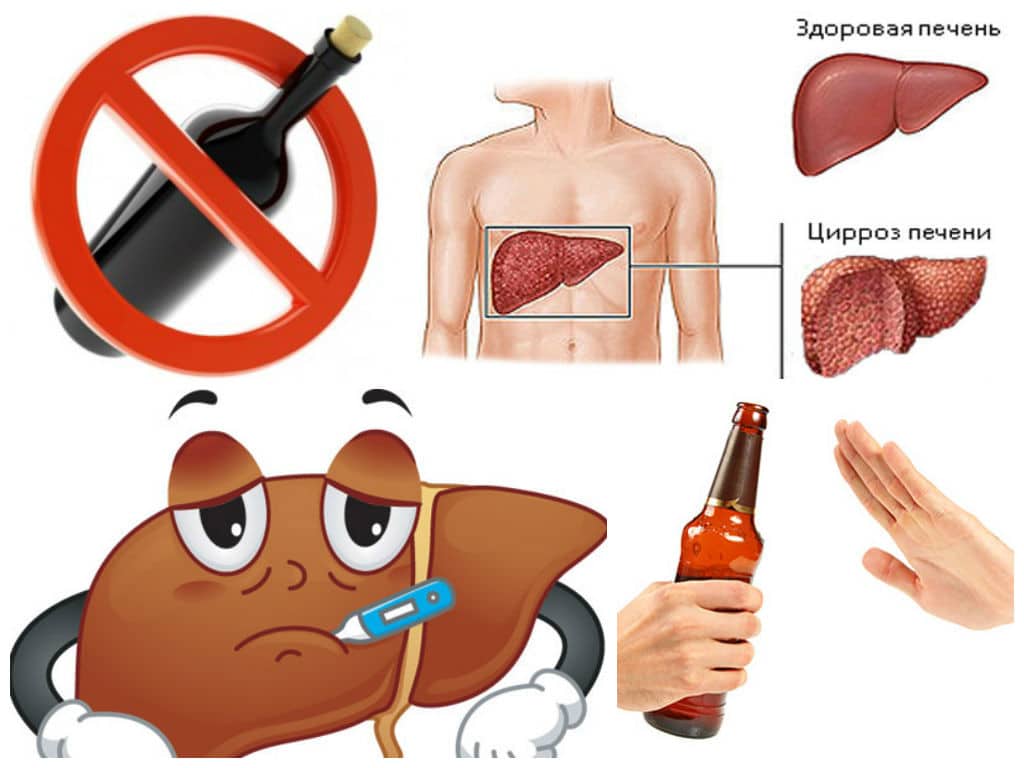

Изображения заболеваний печени: признаки и симптомы